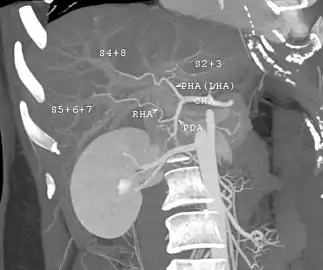

Vascular complications

Vascular complications include thrombosis, stenosis, pseudoaneurysm, and rupture of the hepatic artery.[1] Venous complications occur less often compared with arterial complications, and include thrombosis or stenosis of the portal vein, hepatic vein, or vena cava.[1]

The large majority of liver transplants use the entire liver from a non-living donor for the transplant, particularly for adult recipients. A major advance in pediatric liver transplantation was the development of reduced size liver transplantation, in which a portion of an adult liver is used for an infant or small child. Further developments in this area included split liver transplantation, in which one liver is used for transplants for two recipients, and living donor liver transplantation, in which a portion of a healthy person's liver is removed and used as the allograft. Living donor liver transplantation for pediatric recipients involves removal of approximately 20% of the liver (Couinaud segments 2 and 3).